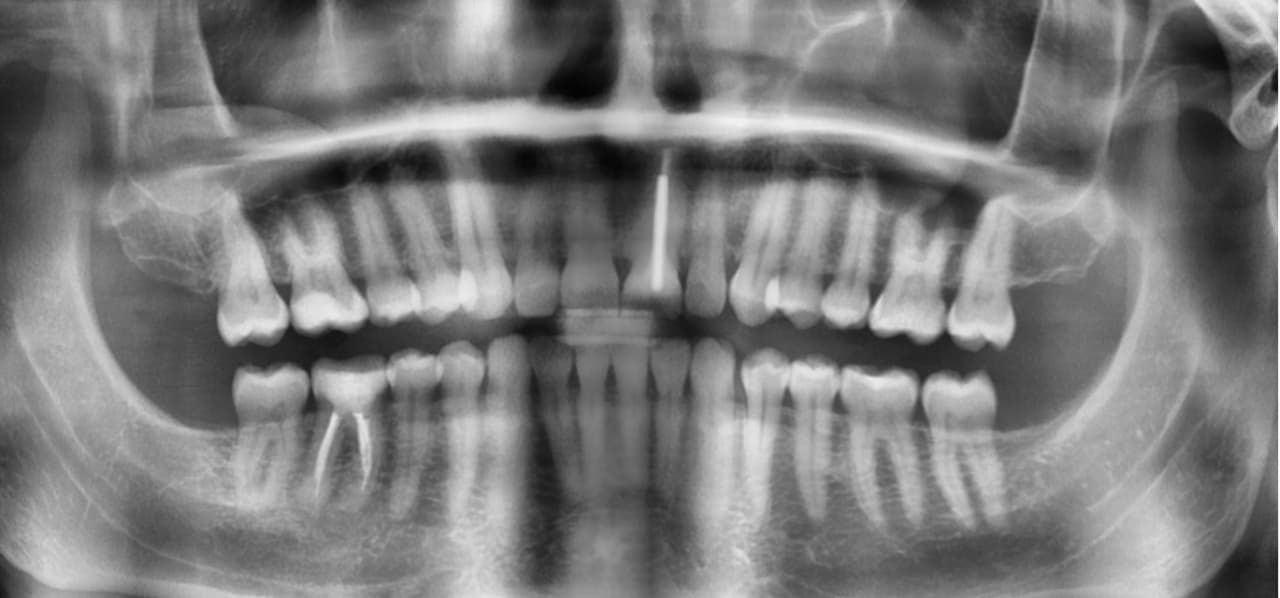

По мере развития пародонтита мы можем видеть убыль костной ткани и обнажающиеся корни зубов. Вместо нормальных десневых сосочков появляются некрасивые чёрные пустые треугольники.

В тяжёлой форме пародонтита, как на иллюстрации выше, можно увидеть очень агрессивную убыль костной ткани. Обратите внимание, что зубы фактически держатся на нижней трети своих корней. Естественно, что никакую нагрузку такие зубы выдерживать уже не могут. Появляется подвижность, которая неизбежно заканчивается тем, что однажды зуб остаётся торчать в яблоке после укуса.